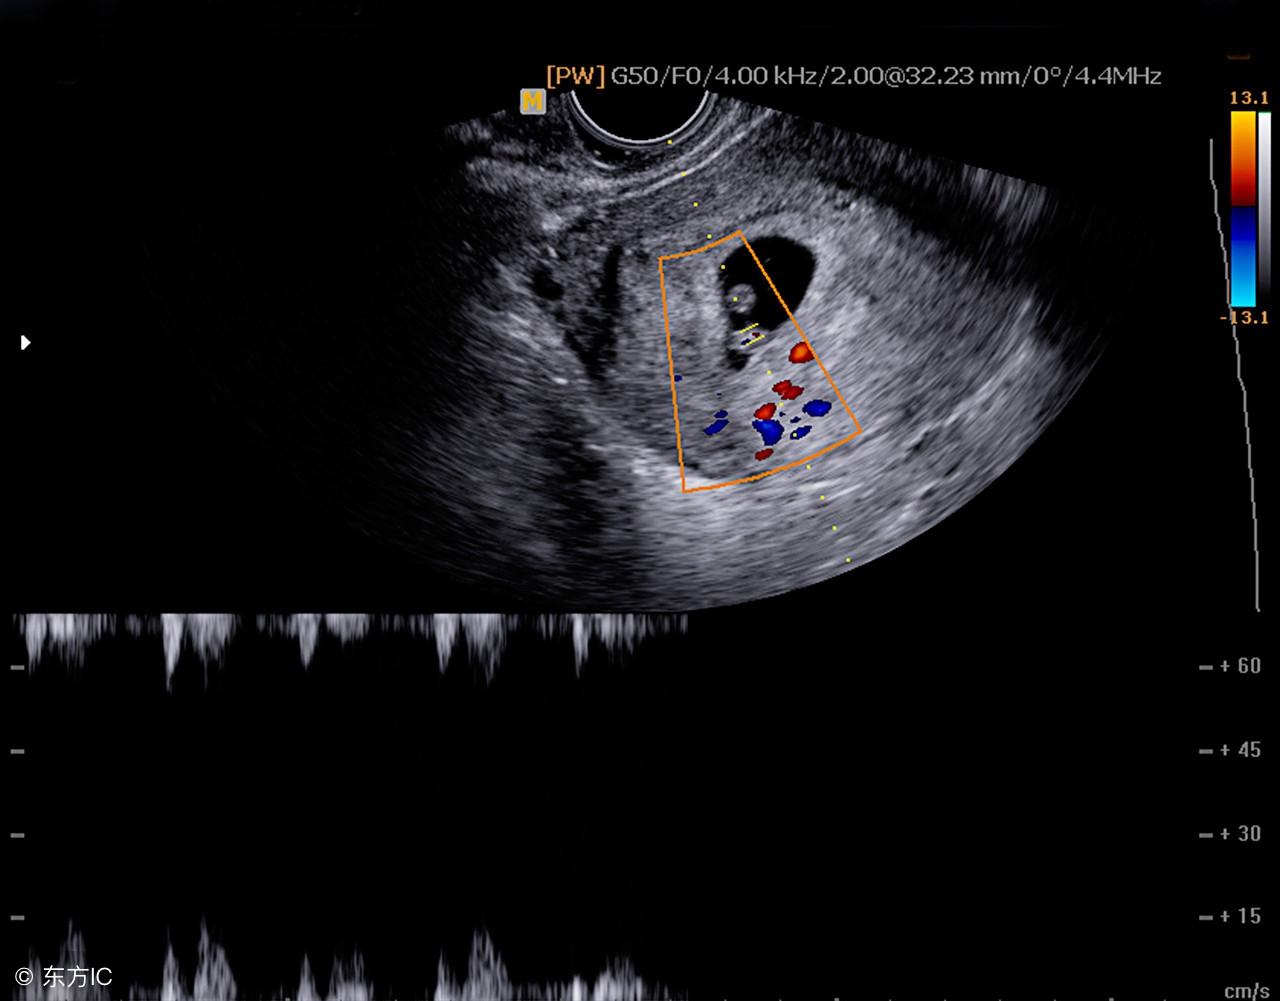

5周:胎儿长到0.4厘米,进入了胚胎期,羊膜腔扩大,原始心血管出现,可有搏动。B超可看见小胎囊,胎囊约占宫腔不到1/4,或可见胎芽。

6周:胎儿长到0.85厘米,胎儿头部、脑泡、额面器官、呼吸、消化、神经等器官分化,B超胎囊清晰可见,并见胎芽及胎心跳。

7周:胎儿长到1.33厘米,胚胎已具有人雏形,体节已全部分化,四肢分出,各系统进一步发育。B超清楚看到胎芽及胎心跳,胎囊约占宫腔的l/3。

8周:胎儿长到1.66厘米,胎形已定,可分出胎头、体及四肢,胎头大于躯干。B超可见胎囊约占官腔1/2,胎儿形态及胎动清楚可见,并可看见卵黄囊。

9周:胎儿长到2.15厘米,胎儿头大于胎体,各部表现更清晰,头颅开始钙化、胎盘开始发育。B超可见胎囊几乎占满宫腔,胎儿轮廓更清晰,胎盘开始出现。

10周:胎儿长到2.83厘米,胎儿各器官均已形成,胎盘雏形形成。B超可见胎囊开始消失,月芽形胎盘可见,胎儿活跃在羊水中 。

11周:胎儿长到3.62厘米,胎儿各器官进一步发育,胎盘发育。B超可见胎囊完全消失,胎盘清晰可见。

12周:胎儿长到4.58厘米,外生殖器初步发育,如有畸形可以表现,头颅钙化更趋完善。颅骨光环清楚,可测双顶径,明显的畸形可以诊断,此后各脏器趋向完善。

GS —— 胎囊,月经规则的妇女,停经35天,B超就可在宫腔内看到孕囊。在怀孕1.5个月时孕囊直径约2厘米,2.5个月时约5厘米。胎囊位置在子宫的宫底、前壁、后壁、上部、中部都属正常;形态圆形、椭圆形、清晰为正常;如胎囊为不规则形、模糊,且位置在下部,孕妇同时有腹痛或阴道流血时,可能要流产。用阴道超声波在四到五周、腹部超声波在六到七周就可以看出并可以描绘出来。到六周以后当子宫内GS看不出来时,可以怀疑是宫外孕。

1、胎囊:胎囊只在怀孕早期见到。在孕1.5个月时直径约2厘米,2.5个月时约5厘米为正常。胎囊位置在子宫的宫底、前壁、后壁、上部、中部都属正常;形态圆形、椭圆形、清晰为正常;如胎囊为不规则形、模糊,且位置在下部,孕妇同时有腹痛或阴道流血时,可能要流产。

3、胎心:有、强为正常,无、弱为异常。胎心频率正常为每分钟120-160次之间。